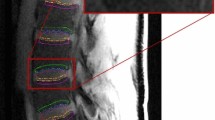

After the incubation chamber had been refilled, T1-weighted dynamic scans were repeated (approximately one every three minutes) for a period of several hours—average period 17 h, longer or shorter according to scanner availability. The parameters of each scan were: TE 3.9 ms, TR 20 ms, flip angle 30°, 30 slices, slice thickness 2 mm, slice overlap 1 mm, FOV 60 × 60 mm, 64 × 64 pixels, resampled to 576 × 576 pixels so as to match the anatomical scan. Example images, showing the time variation of greyscale values in the disc, are given in Fig. 2 (lower panels). The anatomical scan and the dynamic scans were pre-processed using the “CLEAR” function in the Philips imaging software, which corrects the image uniformity on the basis of a coil sensitivity map acquired in a reference scan.

(top left) Central slice from an anatomical scan; (top right) schematic diagram of the 13 disc ROIs; N = nucleus, IA = inner annulus and OA = outer annulus; individual regions are labelled as inner left annulus = ILA, outer posterior annulus = OPA, etc. (the positions of the various regions have not been adjusted to match the anatomical scan); (bottom) central slices at 4-hour intervals from a series of dynamic scans for the diffusion of Gadovist, showing the disc in the centre of the incubation chamber and the oil reference outside; (the bright areas near the chamber walls show regions of incubation medium, where the image slice falls outside the dialysis membranes)

The initial high-resolution anatomical scan of the disc (Fig. 2) allows the annulus, with its distinctive rings, to be distinguished from the nucleus. On the basis of this scan, 13 ROIs were positioned on the central axial slice of each dynamic scan, as shown in Fig. 2; each ROI has approximate volume 2 mm3 (1 mm2 in plane); positions were varied to correspond with the different dimensions of individual discs. For each ROI within each sample, data were obtained on the variation of greyscale values with time, reflecting the diffusion of the active component of the contrast agent into the disc. Examples are given in Fig. 3.